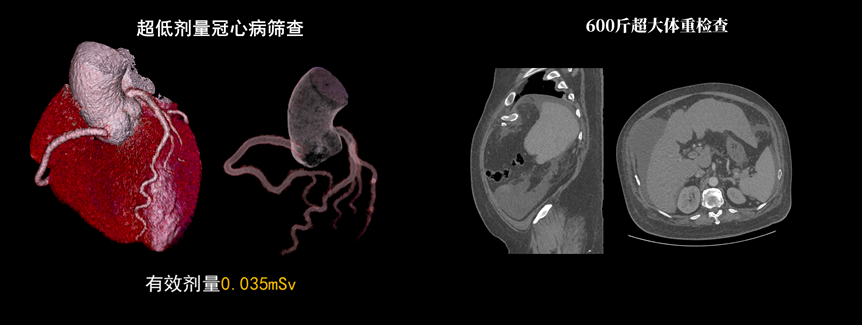

液態(tài)金屬軸承球管,陽極直冷技術(shù),提供30MHU球管熱容量,可高通量連續(xù)掃描。AI劑量調(diào)制、迭代重建等復(fù)合劑量控制方案,為體檢患者提供優(yōu)化劑量掃查。82cm大孔徑,讓大體型患者檢查更加舒適。

天河640CT的寬體探測器單圈掃描即可覆蓋全心臟,搭配快速機(jī)架轉(zhuǎn)速和獨(dú)家AI冠脈追焦技術(shù),可實(shí)現(xiàn)單心動周期內(nèi)無限心率、無限心律的冠脈成像,對于嚴(yán)重心律不齊、房顫、房撲,超高心率等情況,天河640CT都能在單心動周期內(nèi)獲得優(yōu)質(zhì)圖像。